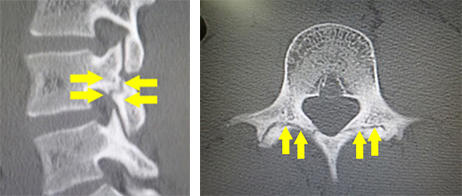

後縦靱帯骨化症、黄色靱帯骨化症

どんな病気?

せぼね(脊椎)は7個の頚椎、12個の胸椎、5個の腰椎と仙椎から構成されます。腰椎は主に5つの骨と、間にあるクッションのような椎間板、また神経組織が通っている脊柱管から成り立っています。後縦靱帯骨化症は椎体の後面で脊髄の前にある後縦靱帯が骨化する病気で、黄色靭帯骨化症は脊髄の後ろにある黄色靭帯が骨化する病気で、頚椎が最も発症頻度が高いですが、胸椎や腰椎にも起こり得ます。いずれも根本的な治療法がないことから、厚生労働省難治性疾患克服研究事業の対象疾患に指定されています。白人に比べて東アジアや日本人に多く、頚椎後縦靱帯骨化症は本邦で約3%、男女比はおおよそ2:1ですが、全身性の骨化では女性に多いことが知られています。家族内発症もあることから遺伝的関与の可能性、そのほか肥満や糖尿病との関連も指摘されています。

検査方法

骨化のタイプや大きさ、不安定性の有無、脊髄の圧迫具合、またせぼね全体のバランスなどを見るためにX線検査やCT検査、MRI検査などを行います。進行例では脊柱管の狭さをより詳しく評価するために入院して脊髄造影検査を行う場合があります。成人期では血管性のしびれがないか評価するために両手足の血圧を測ったり、骨粗鬆症の有無を評価するために骨密度検査を行うこともあります。